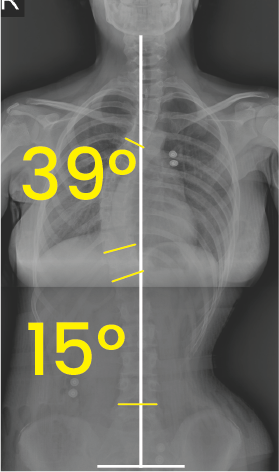

Belirgin 51° ve 32° dereceleri ile işaretlenmiş, omurgada eğriliği gösteren toraks ve karın bölgesi röntgeni.Göğüs ve bel bölgesinde 39° ve 15° eğim açılarını gösteren omurga röntgeni.